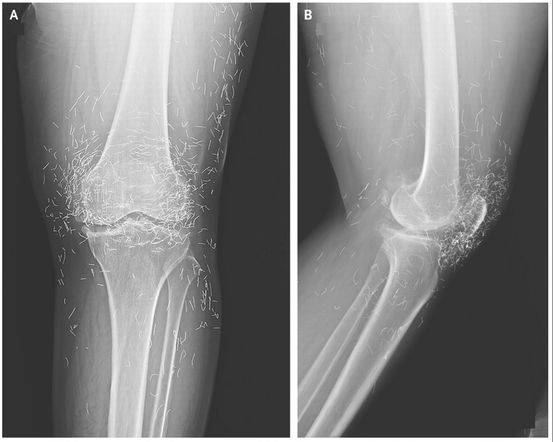

3、直到我膝盖中了很多针……

这张X片展示的是一位韩国65岁妇女的膝盖,密密麻麻的高亮物质是针灸用的金针。

这名妇女之前被诊断为骨关节炎,一种老年关节退行性病变。当镇痛药和抗炎药失效之后,患者采取了针灸治疗。图上的现象不是什么事故,而是针灸师故意留在她膝盖当中进行“持续刺激”的。这种“持续刺激”导致这名妇女发生剧烈的膝盖疼痛,最终不得不就医。

这个案例发表在2013年12月的《新英格兰杂志》上。